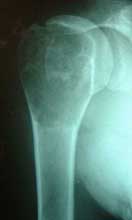

股骨远端骨母细胞瘤        段截肿瘤,大段异体骨移植术后3年愈合良好